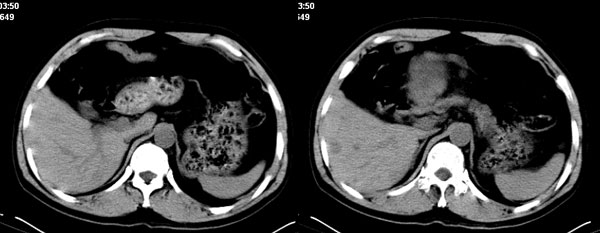

影像学表现:1 腹腔前中部、胰腺前方囊实性病灶(个人认为确定有否实性成分存在这是关键,涉及到鉴别诊断,如果是口服阳性造影剂则可明确左侧是不是小肠了),囊性部分囊壁不均,实性部分有强化,与小肠关系较密切,局部小肠受推移;与胰头、胃后壁均有脂肪间隙存在;2 胰腺无异常改变,胰周无渗出;3肝后段包膜下2个小圆形低密度灶,从图像和楼主提供的ct值来看有轻度强化,灶周无片状强化,不似单纯囊肿及肝癌、炎性病变表现;4 腹膜后及腹腔内无淋巴结肿大。

分析:1 如果腹腔内是囊实性病灶,则应多考虑肿瘤性病变,如源于小肠的间叶源性组织如神经源性肿瘤或间质瘤等;如果这么大存在恶性变的可能,那么肝内则可考虑为转移,征象亦符合;这种可能性最大;

胰腺边界清晰,胰周筋膜不厚,胰周脂肪密度无明显增高;其前方囊实性病灶,边界清晰,增强后实性部分轻度强化;肝内多发边界清晰低密度影,增强后无明显强化(平扫ct值42.9,动脉期48.6,静脉期58.2,延迟期62.2)。

原因:胰头前方,前上腹部巨大囊实性肿物,与小肠关系密切,与胰头及胃壁之间脂肪间隙存在,囊壁不均匀,部分强化,占位效应明显,小肠上段扩张,十二指肠及胃腔内大量食物存留,说明上消化道有部分梗阻。因此,考虑来源于肠道的肿瘤。再结合其病史及肝内改变,这样考虑更有道理。